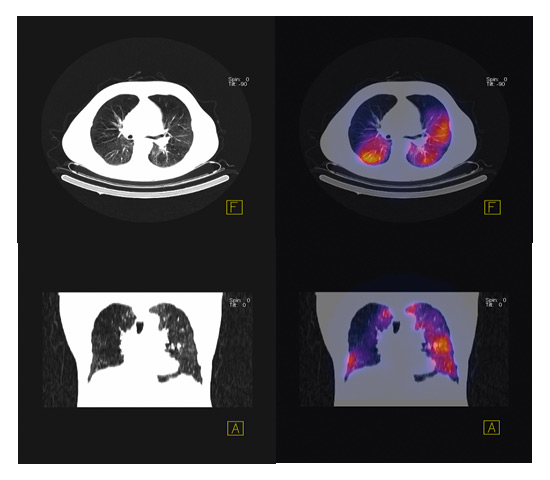

Figure 3

SPECT scan showing heterogeneous emphysema.

What approaches could improve the efficacy of bronchoscopic lung volume reduction? A major advance will be achieved if endobronchial stents used for homogeneous emphysema can be modified to remain open over a longer period of time, so that the initial marked benefit on hyperinflation can be maintained. This could lead to a lasting decrease in hyperinflation and potentially to an improvement in exercise capacity. With respect to valve implantation, the indication for the procedure needs further refining. In a small randomised trial Eberhard et al. showed that complete unilateral lobar exclusion provides better results than bilateral segmental occlusion [12]. Valve placement should primarily target the areas of the lung which are poorly perfused. Thus the optimal placement of valves might not be efficaciously judged by morphology on CT scan only. Figure 3 shows a SPECT (single photon emission tomography) scan which superimposes the morphology on CT scan with the perfusion pattern in a patient with heterogeneous emphysema (courtesy F. Forrer, University Hospital Basel). Seven valves were implanted into the areas of lowest perfusion with the aim of reducing lung volume without loss of diffusion capacity. Valves can therefore be placed not only to the upper but also to the lower lobes [10]. Persistence of collateral ventilation seems to be associated with poorer results of valve implantation as assessed in the US and EuroVENT trials [8]. This problem can be partly overcome by assessing CT scans for total fissures between the different lobes or by evaluating collateral ventilation during bronchoscopy with a specific catheter [13]. An alternative approach to prevention of collateral ventilation is to occlude segments or lobes completely by instilling a polymeric sealant [14, 15] or steam [16]. However, the latter procedure appears to be associated with a marked inflammatory response, thus questioning its clinical value in a patient population already suffering from persistent respiratory symptoms.